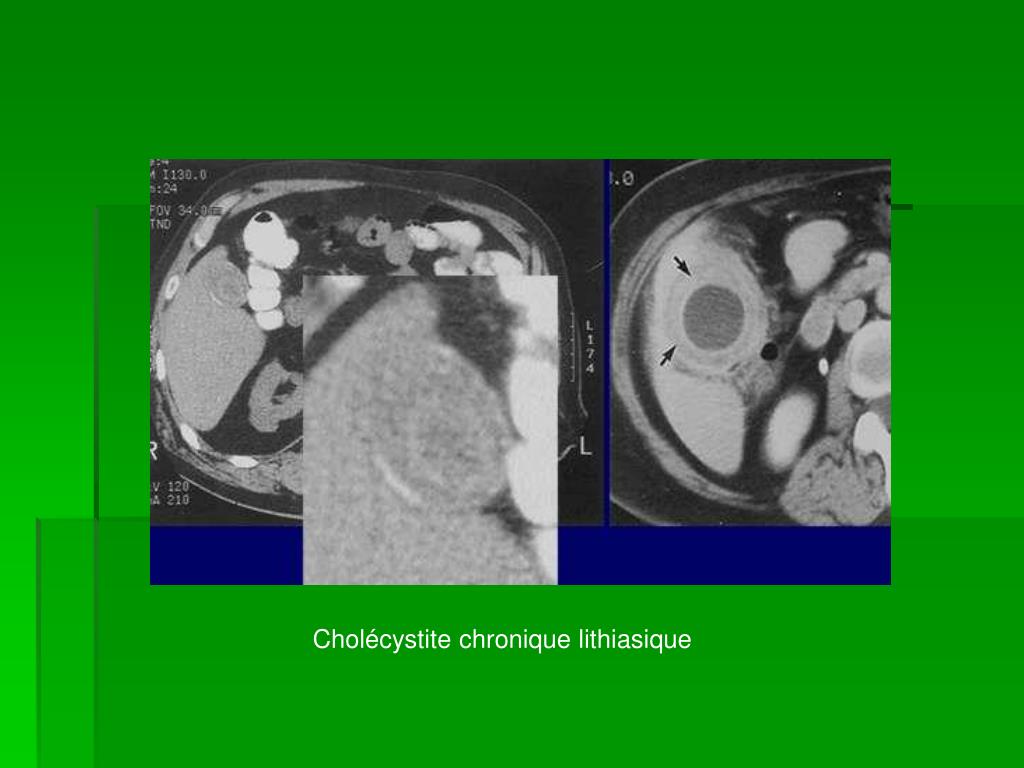

27. Cholécystite chronique Inflammation chronique de la VB, obstruction intermittente du canal cystique par un calcul. • Physiopathologie • Signes cliniquesCrises de foie passagèresExamen clinique fortuit relève un épaississement de la paroi de la VB • Traitement Cholécystectomie par voie coelioscopique (car peut « peut etre » évoluer en cancer)

28. Cholécystite chronique lithiasique